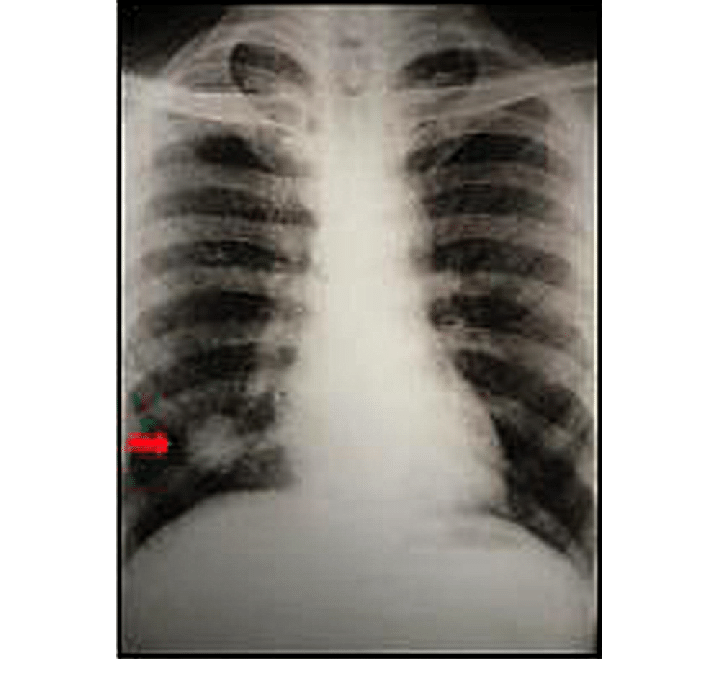

Back in the late 1970s, MD’s mother was diagnosed at age 50 or 51 with a highly undifferentiated adenocarcinoma of the lung. She had no symptoms, and the cancer was diagnosed incidentally on a routine chest x-ray she took annually to prove she didn’t have tuberculosis; she was a teacher and as a person who did not react to the TB skin test, an annual chest x-ray was required.

One year the x-ray turned up what’s known as a ‘coin lesion’ in the upper lobe of her right lung. The name says it all – it’s a bright white perfectly round spot on the lung. The doctors at first assumed it was a metastasis from an adenocarcinoma elsewhere (Breast? Colon? Where?) but further evaluation didn’t turn up anything anywhere else. It was so highly undifferentiated that they couldn’t even identify the cell type (lung, breast, colon, whatever) and this was in the days before they could tissue type from the various antigenic markers that allow them to make such identifications now.